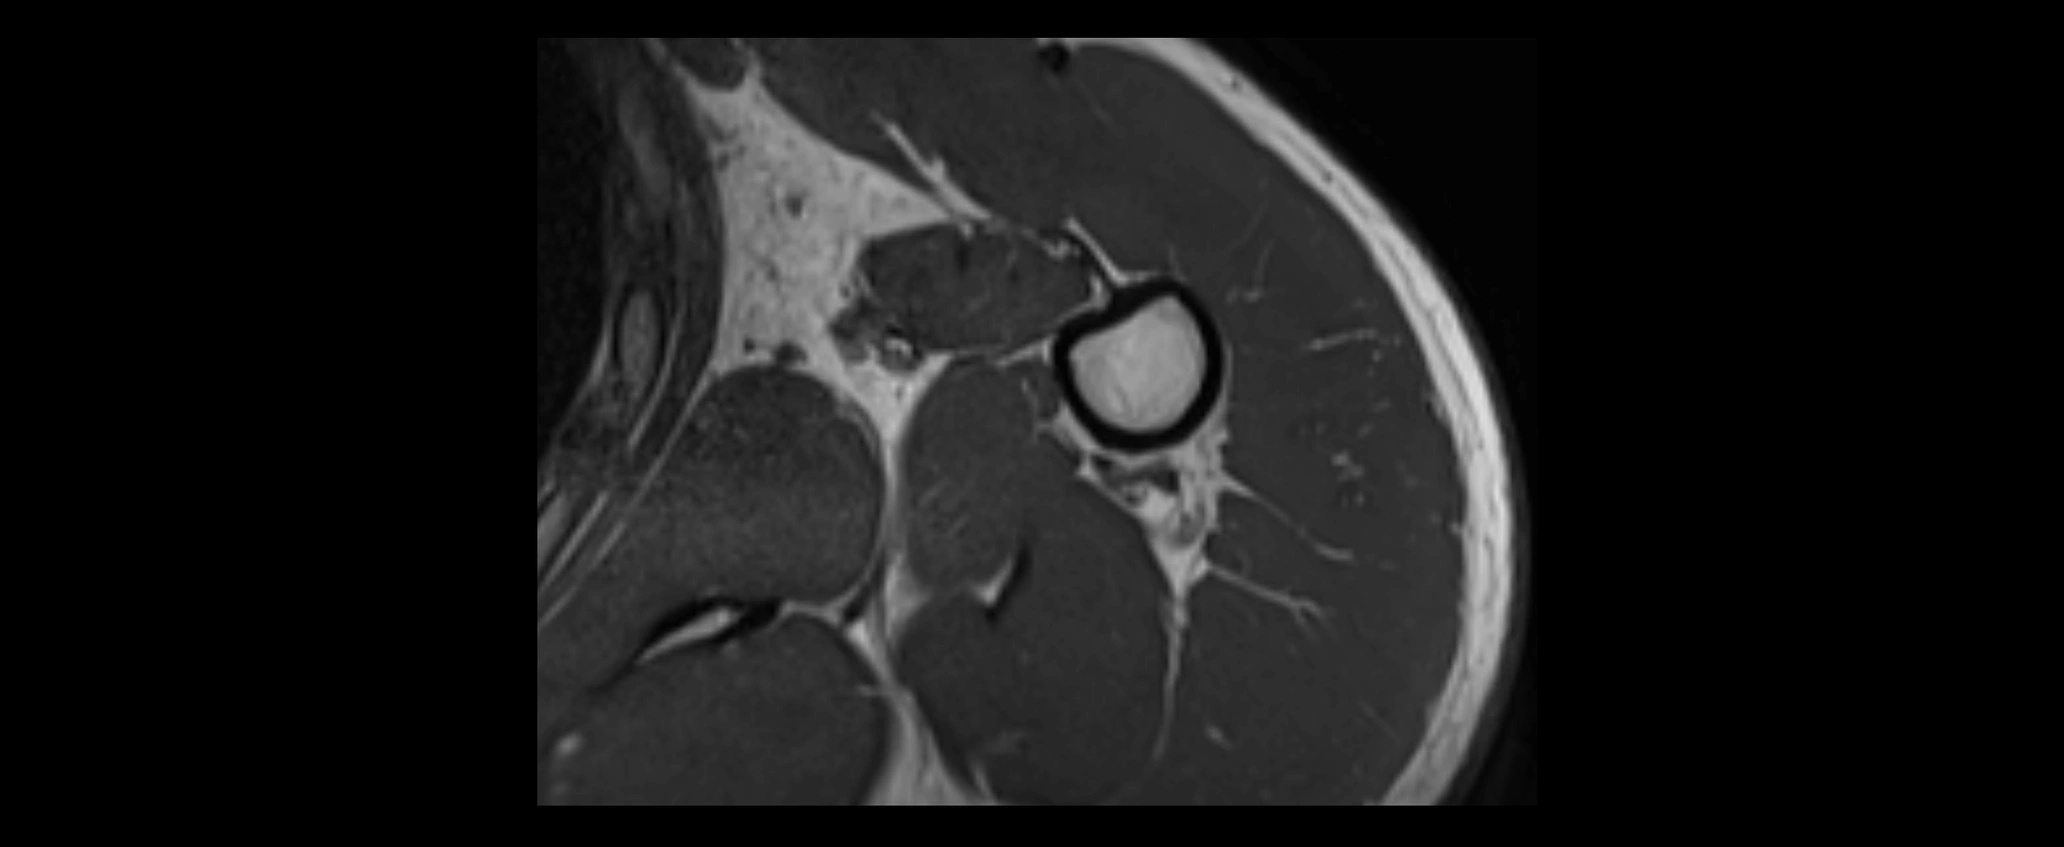

CT image

image